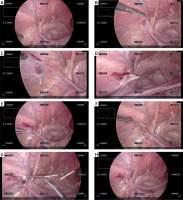

No patient had complications of Clavien–Dindo classification 1 or higher. In all cases, the surgery could be completed with the scope remaining fixed in position, using eye guidance and voice instructions to magnify and move the displayed endoscopic image (Photo 3) (Supplementary Material 2). The median number of voice commands used per LPEC for one side was 15 (range: 10–22). The displayed image was digitally zoomed up to 2.5× (screen resolution of 1534 × 864 pixels). The surgeon completed all surgical procedures alone, including needle manipulation, except when the patient’s testes were in traction.

Photo 3

Representative monitor images obtained when using the system during LPEC. In all of these images, manipulation of magnification and image movement was performed solely by voice recognition and eye tracking, with the scope fixed. A – The camera is fixed so that the entire operative field, centered on the inner groin ring, is captured in the image. B – The internal inguinal ring is observed by magnifying the image. C – The needle tip is followed while magnifying and moving the image. D – The needle tip punctures the abdominal cavity. E – The image is then zoomed out to include the entire area. F – Movement of the needle tip is followed with magnification and movement of the image. G – Retrieval of the thread in the abdominal cavity. H – Ligation of the internal inguinal ring